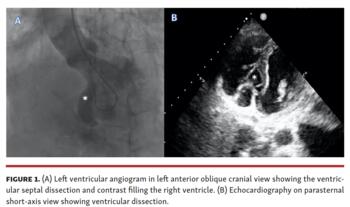

A 57-year-old female patient presented to the emergency room with acute-onset dyspnea for 2 days. She was thrombolyzed with streptokinase 4 days prior for inferior wall myocardial infarction (MI) in a nearby hospital. Her exam showed elevated jugular venous pressure and systolic murmur in the left lower parasternal region. Electrocardiogram showed Q waves in inferior leads. Echocardiography (Figure 1B; Video 1) showed an akinetic inferior wall. In addition, there was a ventricular septal rupture in the posterobasal interventricular septum, with at least 2 exit points into the right ventricle. The posterobasal appeared to have dissected, leading to communication between the left and right ventricles. Coronary angiography showed a normal left coronary artery and complete occlusion of the right coronary artery (RCA). There were no collaterals from the left system to the RCA. Left ventricular angiogram (Figure 1A; Video 1) was done with a pigtail catheter, which showed ventricular septal defect with diffuse contrast filling of the right ventricle. This was suggestive of multiple entry points into the right ventricle. Since there were multiple exit points, device closure could not be contemplated. The patient was stabilized with optimal medical therapy and planned for ventricular septal repair after 28 days, as in the immediate aftermath of ST-segment elevation MI, the septum will be friable and increase the difficulty of suture application. The patient underwent patch repair elsewhere and is currently doing well.